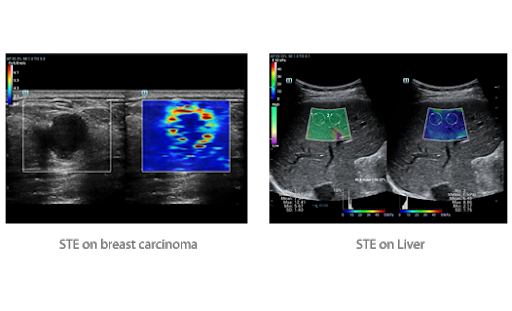

Эластография Sound Touch

Технология Shear Wave Elastography (эластография с использованием сдвиговых волн) системы Resona 7 основана на эксклюзивном решении компании Mindray — Ultra Wide Beam Tracking (ультраширокий контроль луча), повышающем скорость формирования изображенияи четкость визуализациипри абдоминальныхисследованиях, а также исследованиях малых органов. Визуализация осуществляется в режиме реального времени с использованием комплексных количественных показателей для повышения точности диагностики.